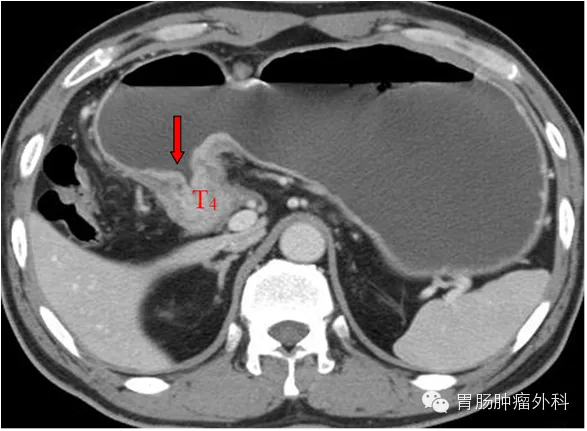

2、螺旋CT检查,可评价胃癌病变范围、局部淋巴结转移和远处转移。是判断胃癌术前临床分期的首选方法 。